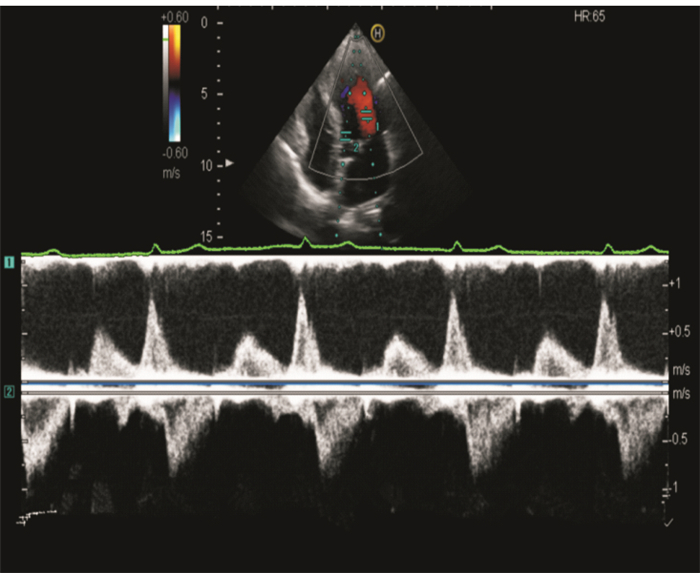

采用HITACHI Ascendus多普勒超聲診斷儀,S5-1探頭,頻率2.0~4.0 MHz。檢查前常規測量受檢者身高、體重、血壓、心率。取左側臥位,平靜呼吸,連接同步心電圖,于胸骨旁左室長軸切面測量常規超聲指標:左心房內徑(left atrial diameter, LAD)、左室舒張末期內徑(left ventricular end-diastolic diameter, LVEDD)、舒張期室間隔厚度(interventricular septum thickness at end-diastole, IVSD)及左室后壁厚度(posterior wall thickness, PWD),計算左室舒張末期容積指數(left ventricular end-diastolic volume index, LVEDVI), LVEDVI=LVEDV/BSA。于心尖四腔心切面,開啟PW/DTI同步取樣技術,取樣容積分別置于二尖瓣口及二尖瓣前瓣環,同時記錄二尖瓣前向血流頻譜及二尖瓣前瓣環組織多普勒頻譜,于同一心動周期測量二尖瓣前向血流舒張早、晚期峰值流速(E峰、A峰)、減速時間(deceleration time, DT)、二尖瓣前瓣環舒張早期峰值速度(e’峰),計算E/A比值、E/e’比值、Tei指數、E峰與e’峰的起始時間差(TE-e’)(見圖 1)。于心尖五腔心切面,將脈沖多普勒取樣線置于二尖瓣口與左室流出道之間,獲得左室流入與流出道血流頻譜,測量左室等容舒張時間(isovolumic relaxation time, IVRT)(見圖 2)。雙平面Simpson's法測量左室射血分數(left ventricular ejection fraction, LVEF)。